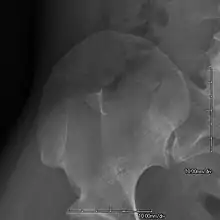

- Exostoses arising from the posterior aspect of the iliac bones ("iliac horns") are present in as many as 80% of patients; this finding is considered pathognomonic for the syndrome.

This is a view from a different angle of the same man's other elbow

The hallmark features of this syndrome are poorly developed fingernails, toenails, and patellae (kneecaps). Sometimes, this disease causes the affected person to have either no thumbnails or a small piece of a thumbnail on the edge of the thumb. The lack of development or complete absence of fingernails results from the loss of function mutations in the LMX1B gene. This mutation may cause a reduction in dorsalising signals, which then results in the failure to normally develop dorsal specific structures such as nails and patellae.[11] Other common abnormalities include elbow deformities, abnormally shaped pelvic (hip) bones, and kidney disease.